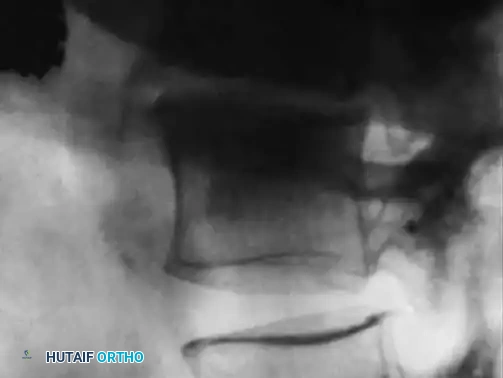

Late radiographic findings (often taking up to 2 years to fully manifest) include vertebral body collapse, segmental kyphosis, and spontaneous bony ankylosis.

Fig. 40-7C: After successful treatment and eradication of the infection, note the sclerotic vertebra and the formation of a large bridging osteophyte indicating spontaneous fusion.